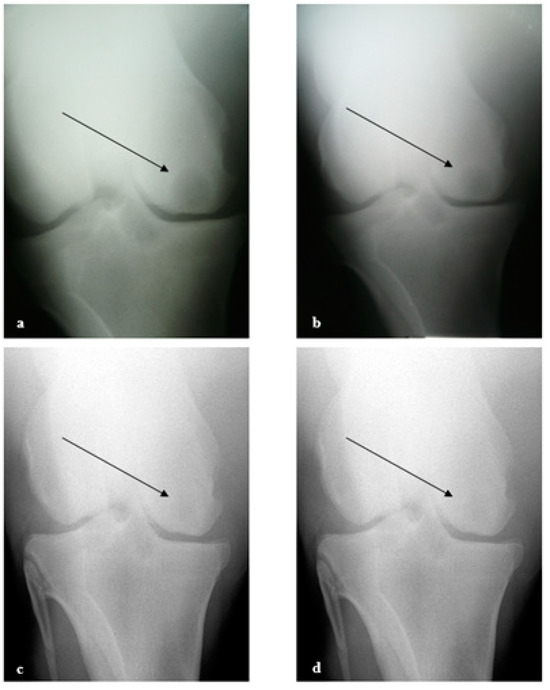

2.5. Radiographic Analysis

3.1. Bone Cyst Treatment

3.2. Clinical Evaluation